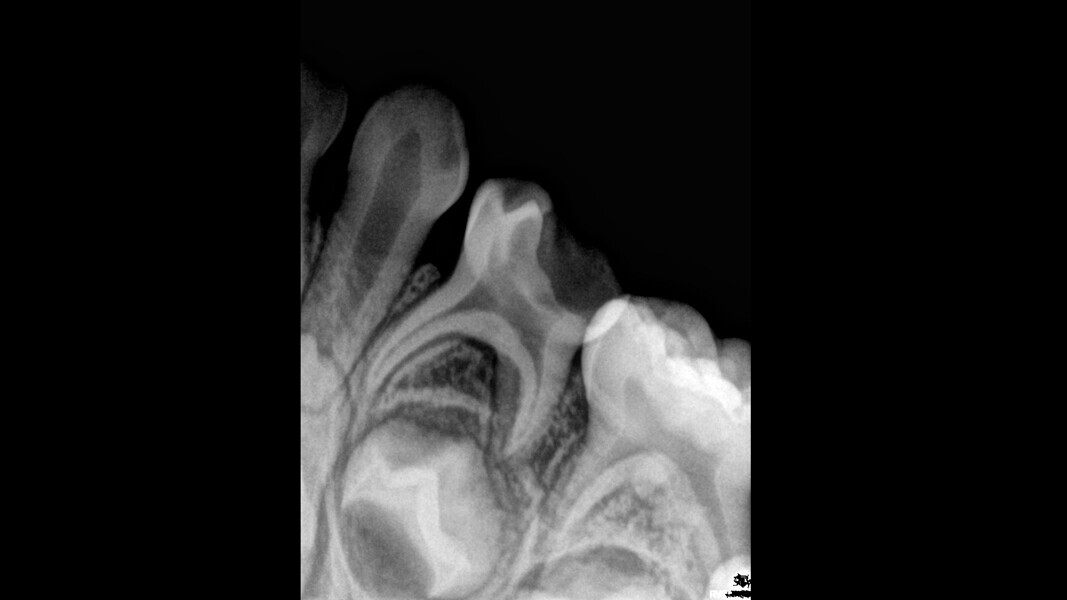

Case 1 (Figs. 1–4)

This female patient was 4 years and 7 months old and presented with pain that had lasted for several days affecting the mandibular right second primary molar. On clinical examination, a buccal gingival swelling and facial initial oedema were noted, and the tooth was found to have deep occlusal decay. Pulp necrosis and a symptomatic apical abscess were diagnosed. The patient was prescribed medication to control acute infection and rescheduled after the antibiotic treatment. At the second appointment, no pain was reported and the buccal abscess had partially receded. A decision was made to perform pulpectomy and restoration. Over-extrusion of the obturation material was observed. The 15-month re-evaluation confirmed no clinical or radiological signs of disease, and bone deposition was evident in the furcal area.